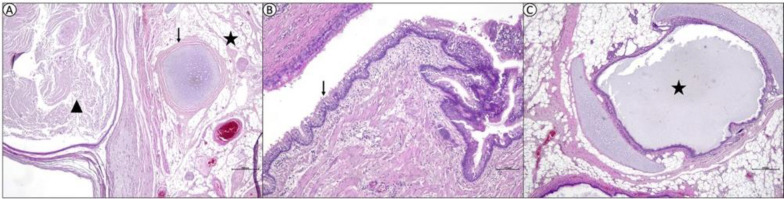

Case description: In this report, a 5-month-old kitten was brought to the clinic with the complaint of difficulty breathing, food intake, and oropharyngeal mass. In clinical examination, there was a large mass, protruding from the localization included left buccal mucosa, soft palate, and extending into the oropharynx but no cranial extension was observed in CT scans. The mass was completely resected. Macroscopically, the mass measured 4.5 × 6.5 cm2 and contained solid and cystic areas associated with soft and hard tissue components.

Findings/treatment and outcome: Histopathology revealed an extragonadal solid-cystic (grade 0) oropharyngeal mature teratoma containing structures from endoderm, mesoderm, and ectoderm. After an 8-month follow-up control period, no signs of recurrence were observed.

Conclusion: The case was deemed worthy of being presented with its clinical, radiological, and pathological findings, and complete resection was curative for mature teratoma.